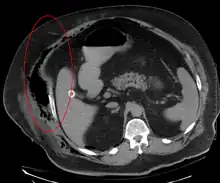

Imaging has a limited role in the diagnosis of necrotizing fasciitis. The time delay in performing imaging is a major concern. Plain radiography may show subcutaneous emphysema (gas in the subcutaneous tissue), which is strongly suggestive of necrotizing changes, but it is not sensitive enough to detect all the cases, because necrotizing skin infections caused by bacteria other than clostridial infections usually do not show subcutaneous emphysema. If the diagnosis is still in doubt, computed tomography (CT) scans and magnetic resonance imaging (MRI) are more sensitive modalities than plain radiography. However, both the CT scan and MRI are not sensitive enough to rule out necrotizing changes completely.[2] CT scan may show fascial thickening, edema, subcutaneous gas, and abscess formation.[2] In MRI, when fluid collection with deep fascia involvement occurs, thickening or enhancement with contrast injection, necrotizing fasciitis should be strongly suspected. Meanwhile, ultrasonography can show superficial abscess formation, but is not sensitive enough to diagnose necrotizing fasciitis.[2] CT scan is able to detect about 80% of cases, while MRI may pick up slightly more.[14]